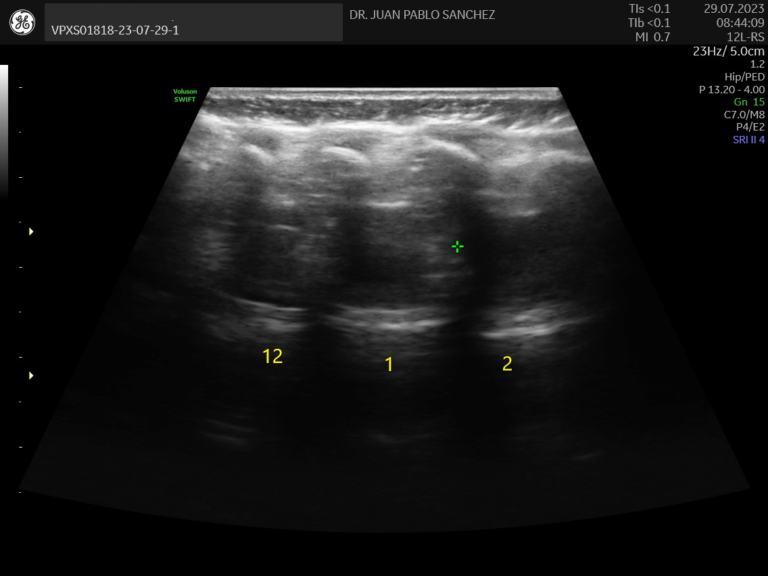

Ecografia de caderas

Estudio esencial en bebés para detectar displasia del desarrollo de cadera. Es indolora y se realiza idealmente en los primeros meses de vida como parte del control del niño sano.